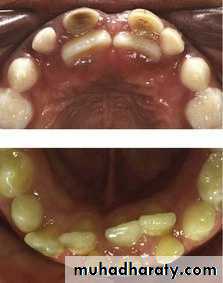

6- Early loss of primary tooth

• 5- Transposed teeth.• 6- Uneven resorption of deciduous roots.

• 7- Prolonged retention of primary teeth.

• 8- interproximal caries if not restored.

• 9- Abnormal exfoliation sequence.

• 10- Altered eruption sequence.